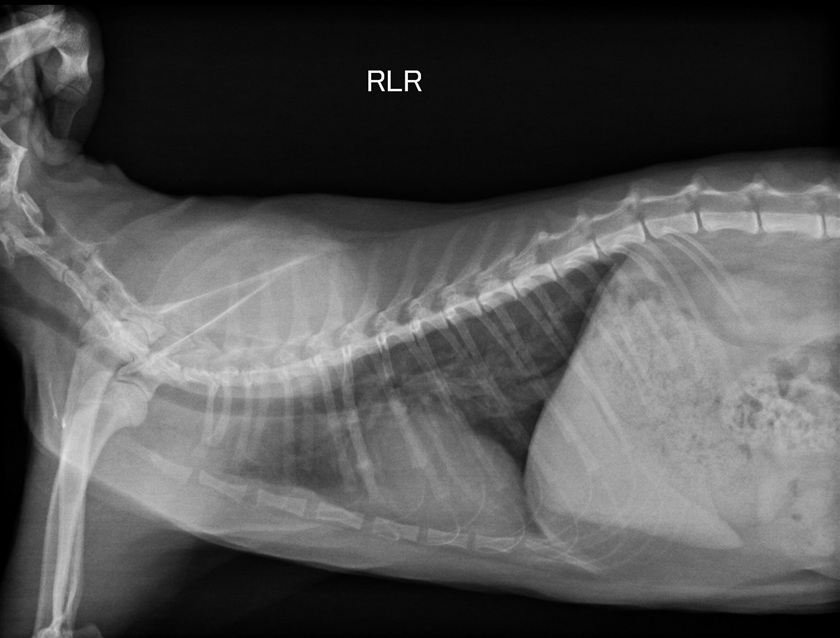

8/3回診- 4.45kg

罔市離上次回診已過了半年,

為確認目前的心臟狀況而回診做各項檢查。

檢查項目有測血壓140 (正常),

拍X光照片和心電圖超音波,

醫生認為心臟狀況看起來還不錯,

但目前還是需要持續服用心臟藥以維持正常的機能,

不過活動方式都可以繼續和之前一樣,

有照護員在時可讓罔市出籠活動活動。

醫生認為罔市之後是可能有可以停藥的一天,

不過要視之後回診的檢查結果作評估,

下次回診為半年後。